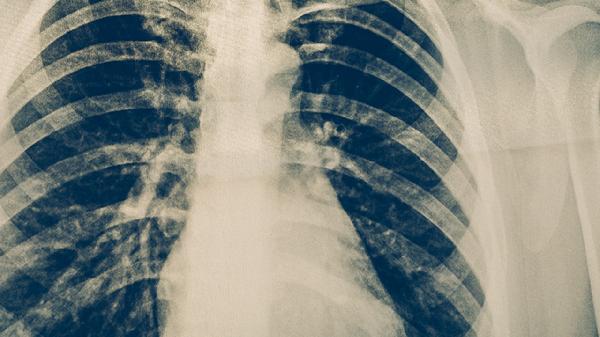

3、病情进展

胸部CT显示原有空洞扩大或新发浸润灶,可能伴随胸膜增厚或支气管扩张。广泛耐药结核病易导致双肺多叶受累,部分患者会出现氧分压降低等呼吸功能受损表现。此时需考虑使用注射用阿米卡星等静脉给药方案。